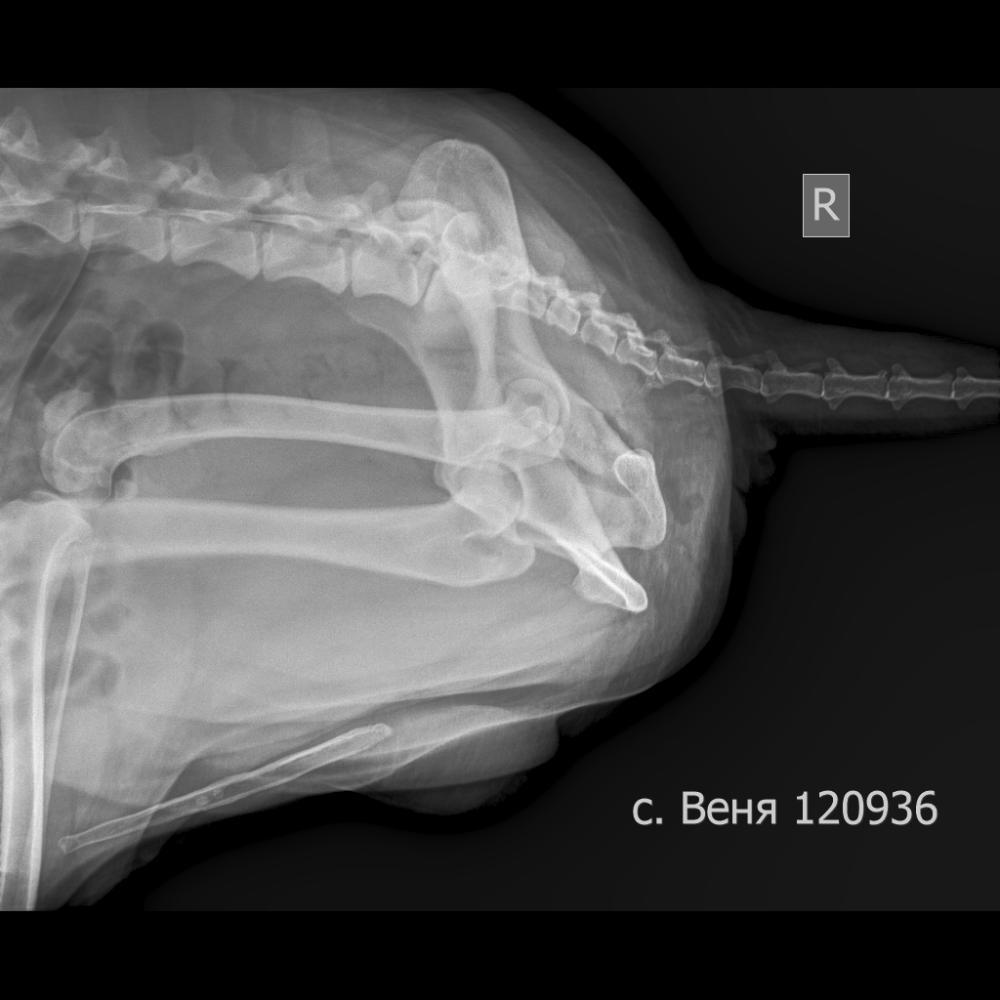

Рентген:

Тени органов видимой части брюшной полости

визуализируются чётко. В видимой части петель

тонкого отдела кишечника определяются

однородные массы и газ. В видимой части толстого

отдела кишечника визуализируются каловые массы

и газ. Не выявлено признаков механической

непроходимости видимого участка ЖКТ на момент

исследования. Стоит учитывать возможность

наличия неконтрастных инородных предметов,

которые невидимы на рентгенограммах. Видимая

часть селезёнки визуально без отклонений. Тени

почек вне зоны коллимации. Не выявлено

изменений в области проекции мочеточников.

Мочевой пузырь наполнен, в его проекции

визуализируются множественные дополнительные

тени повышенной рг-плотности - уролиты,

минерализованный осадок. Простатомегалия. В

суперимпозиции с средней третью половой кости

визуализируются две дополнительные округлые

тени повышенной рг-плотности - уролиты в уретре.

Описанные находки не исключают наличие

уратных, цистеиновых и прочих

нерентгеноконтрастных включений. Объёмные

образования в видимой части брюшной полости не

выявлены, что не исключает наличие образований с

низкой рентгенологической плотностью и низким

масс-эффектом, а также наличие образований вне

зоны коллимации. Поверхностные ткани без

рентгенографических отклонений. Все костные

структуры соответствуют породе и возрасту.

Более значимых находок не выявлено. Учитывайте

чувствительность и специфичность данного метода

исследования. В ходе интерпретации

рентгеновских снимков были описаны

предварительные диагнозы, которые объясняют

находки на снимках. Диагноз не является

окончательным и должен быть интерпретирован

лечащим врачом на основании клинических и

анамнестических данных.